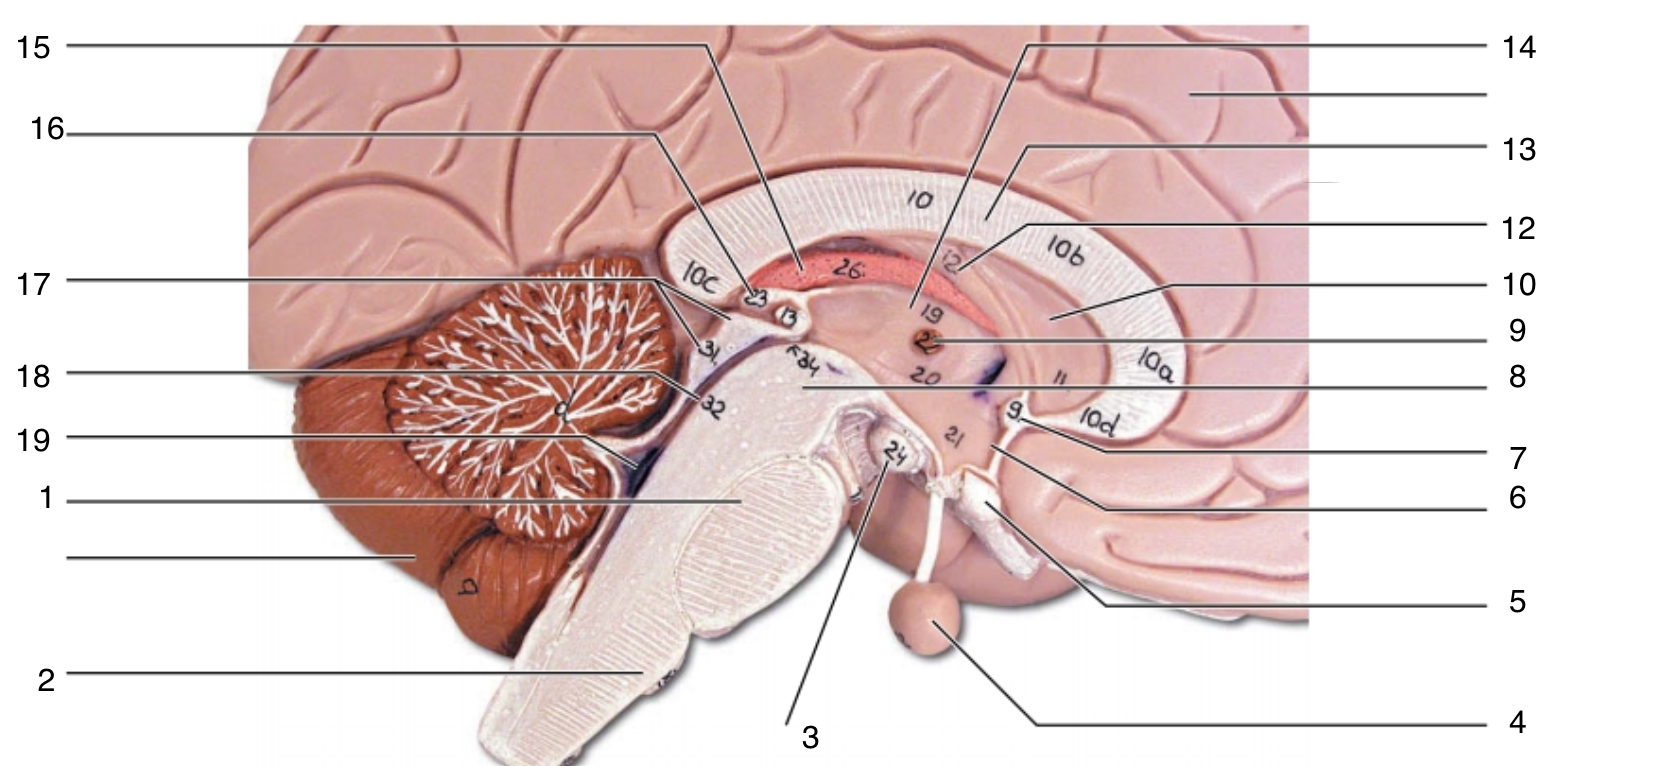

Brain Stem

1

pons

1

2

medulla oblongata

2

3

mammillary body

3

4

pituitary gland

4

5

optic chiasma

5

6

hypothalamus

6

7

anterior commissure

7

8

midbrain

8

9

interthalamic adhesion

9

10

septum pellucidum

10